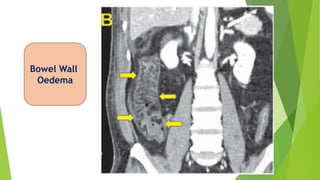

CECT abdomen

Bowel Wall

Oedema